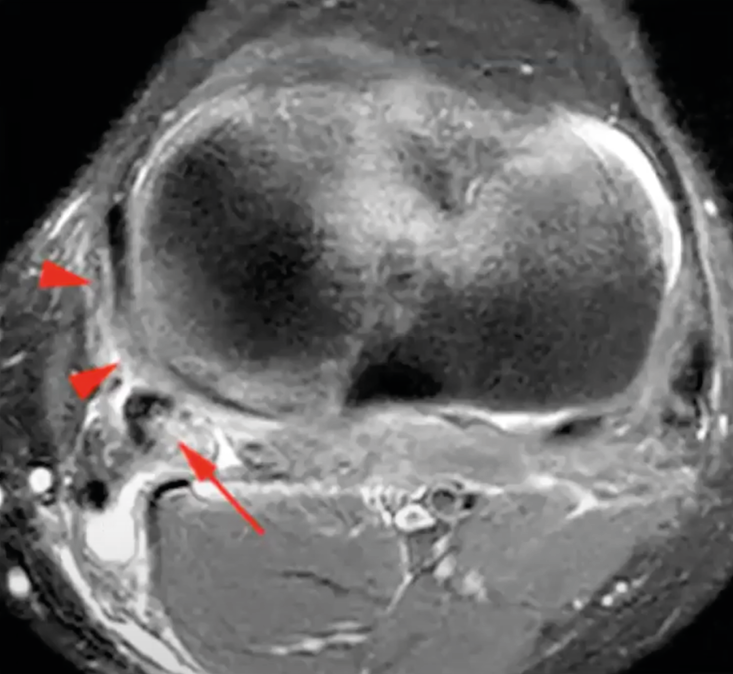

On the axial images, the point of the posteromedial corner can be seen, including: POL, posteromedial joint capsule, posterior horn of medial meniscus, semimembranosus. If there is an injury, these structures will appear with low signal intensity on all sequences (Figure 11) [9] Fusco S, Albano D, Gitto S, Serpi F, Messina C, Sconfienza LM. Posteromedial Corner Injuries of the Knee: Imaging Findings. Semin Musculoskelet Radiol. juin 2024;28(3):318-26. .

Finally, MRI can be used to look for a Stener-like lesion, which is entrapment of MCL between the torn structures at the tibia, which can occur under the hamstrings, within the joint or under the medial meniscus (Figure 12).